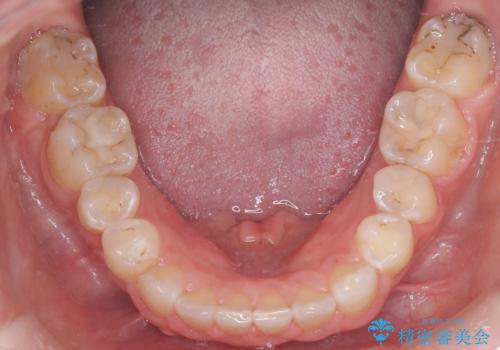

今回の矯正治療では、歯が並ぶスペースを確保するため、上顎の小臼歯を抜歯しました。抜歯によってできたスペースを有効活用し、ワイヤーやブラケットを使って右上の八重歯を適切な位置へ移動させ、叢生を解消していきました。また、治療を通じて上下の歯の中心である正中線のズレも改善するよう、慎重に歯を動かしました。治療の結果、長年気にされていた八重歯と歯のデコボコが解消され、上下の正中線も一致。機能的にも審美的にもバランスの取れた、美しい歯並びと笑顔を獲得していただけました。